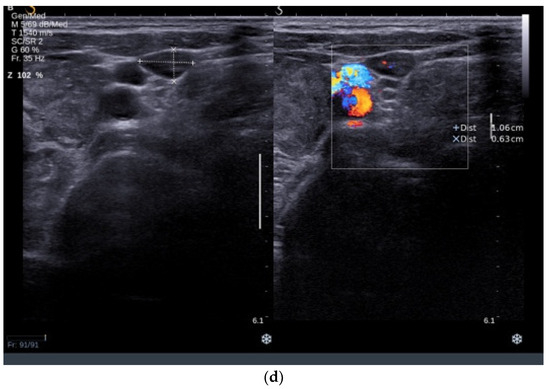

3.3.2. Thyroid Ultrasound